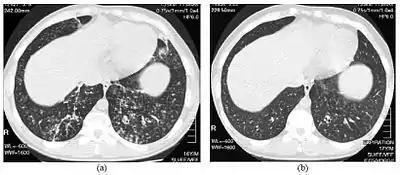

High resolution computed tomography (HRCT) images of the lower chest in a 16-year-old boy initially diagnosed with DPB (left), and 8 weeks later (right) after a 6-week course of treatment with erythromycin. The bilateral bronchiectasis and prominent centri-lobular nodules with a "tree-in-bud" pattern shows noticeable improvement.

The diagnosis of DPB requires analysis of the lungs and bronchiolar tissues, which can require a lung biopsy, or the more preferred high resolution computed tomography (HRCT) scan of the lungs.[7] The diagnostic criteria include severe inflammation in all layers of the respiratory bronchioles and lung tissue lesions that appear as nodules within the terminal and respiratory bronchioles in both lungs.[4] The nodules in DPB appear as opaque lumps when viewed on X-rays of the lung, and can cause airway obstruction, which is evaluated by a pulmonary function test, or PFT.[6] Lung X-rays can also reveal dilation of the bronchiolar passages, another sign of DPB. HRCT scans often show blockages of some bronchiolar passages with mucus, which is referred to as the "tree-in-bud" pattern.[7] Hypoxemia, another sign of breathing difficulty, is revealed by measuring the oxygen and carbon dioxide content of the blood, using a blood test called arterial blood gas. Other findings observed with DPB include the proliferation of lymphocytes (white blood cells that fight infection), neutrophils, and foamy histiocytes (tissue macrophages) in the lung lining. Bacteria such as H. influenzae and P. aeruginosa are also detectable, with the latter becoming more prominent as the disease progresses.[4][5] The white blood, bacterial and other cellular content of the blood can be measured by taking a complete blood count (CBC). Elevated levels of IgG and IgA (classes of immunoglobulins) may be seen, as well as the presence of rheumatoid factor (an indicator of autoimmunity). Hemagglutination, a clumping of red blood cells in response to the presence of antibodies in the blood, may also occur. Neutrophils, beta-defensins, leukotrienes, and chemokines can also be detected in bronchoalveolar lavage fluid injected then removed from the bronchiolar airways of individuals with DPB, for evaluation.[4][9]